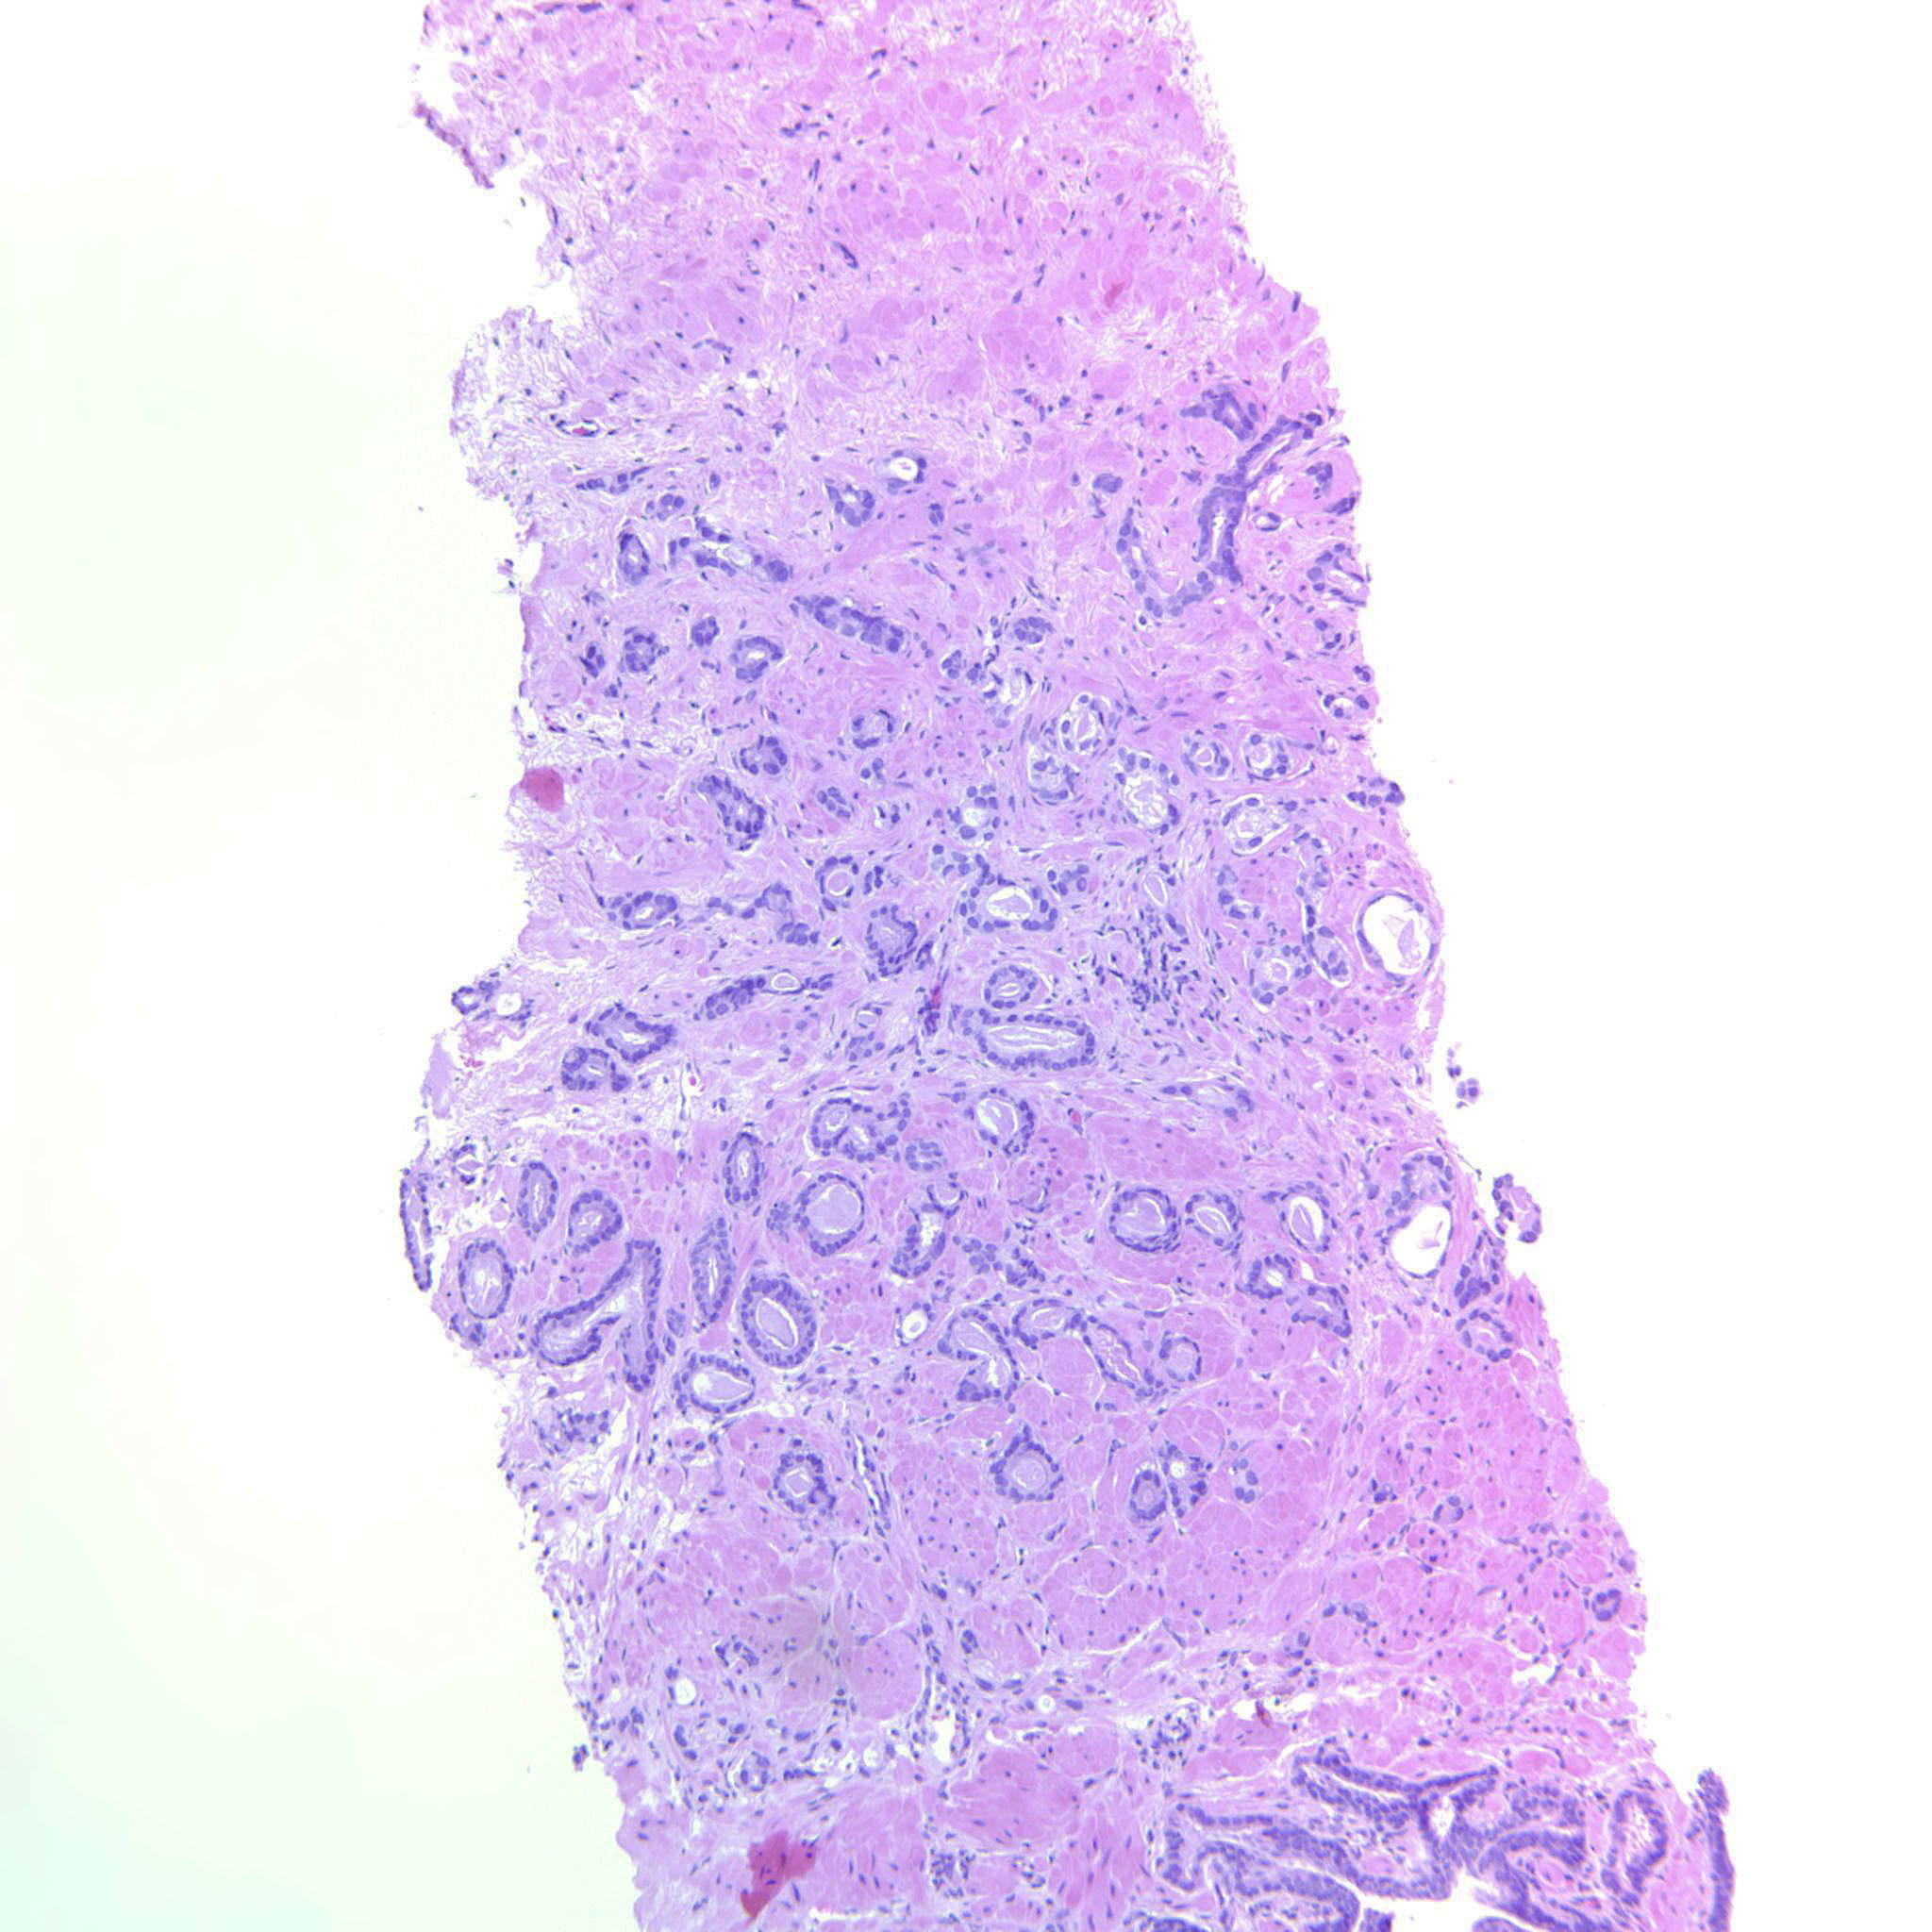

Consensus grade: GS 3+3=6 (ISUP 1)

Show diagnosis by expert panel members| User | Diagnosis | Difficulty | Comment |

|---|---|---|---|

| Pathologist 1 | GS 3+3=6 (ISUP 1) | Borderline higher |

? poorly formed glands |

| Pathologist 2 | GS 3+3=6 (ISUP 1) | Typical | |

| Pathologist 3 | GS 3+3=6 (ISUP 1) | Borderline higher | |

| Pathologist 4 | GS 3+4=7 (ISUP 2) | Typical | |

| Pathologist 5 | GS 3+3=6 (ISUP 1) | Borderline higher | |

| Pathologist 6 | GS 3+3=6 (ISUP 1) | Typical | |

| Pathologist 7 | GS 3+3=6 (ISUP 1) | Typical |

Few slightly poorly formed glands but still a 3 |

| Pathologist 8 | GS 3+4=7 (ISUP 2) | Typical | |

| Pathologist 9 | GS 3+3=6 (ISUP 1) | Borderline higher | |

| Pathologist 10 | GS 3+3=6 (ISUP 1) | Borderline higher | |

| Pathologist 11 | GS 3+3=6 (ISUP 1) | Typical |

atrophic G3 |

| Pathologist 12 | GS 3+4=7 (ISUP 2) | Borderline lower | |

| Pathologist 13 | GS 3+4=7 (ISUP 2) | Typical | |

| Pathologist 14 | GS 3+3=6 (ISUP 1) | Typical | |

| Pathologist 15 | GS 3+4=7 (ISUP 2) | Borderline higher |

Approx.10% pattern 4 |

| Pathologist 16 | GS 3+3=6 (ISUP 1) | Borderline higher | |

| Pathologist 17 | GS 3+4=7 (ISUP 2) | Typical | |

| Pathologist 18 | GS 3+3=6 (ISUP 1) | Borderline higher | |

| Pathologist 19 | GS 3+4=7 (ISUP 2) | Typical | |

| Pathologist 20 | GS 3+4=7 (ISUP 2) | Borderline higher | |

| Pathologist 21 | GS 3+3=6 (ISUP 1) | Typical |

would give comment on stroma |

| Pathologist 22 | GS 3+3=6 (ISUP 1) | Typical | |

| Pathologist 23 | GS 3+3=6 (ISUP 1) | Borderline higher | |

| Pathologist 24 | GS 3+3=6 (ISUP 1) | Borderline higher |

Case description (by case creator):

Circumscribed cancer glands. Occasional seemingly solid strips of epithelium that may be tangential cuts.